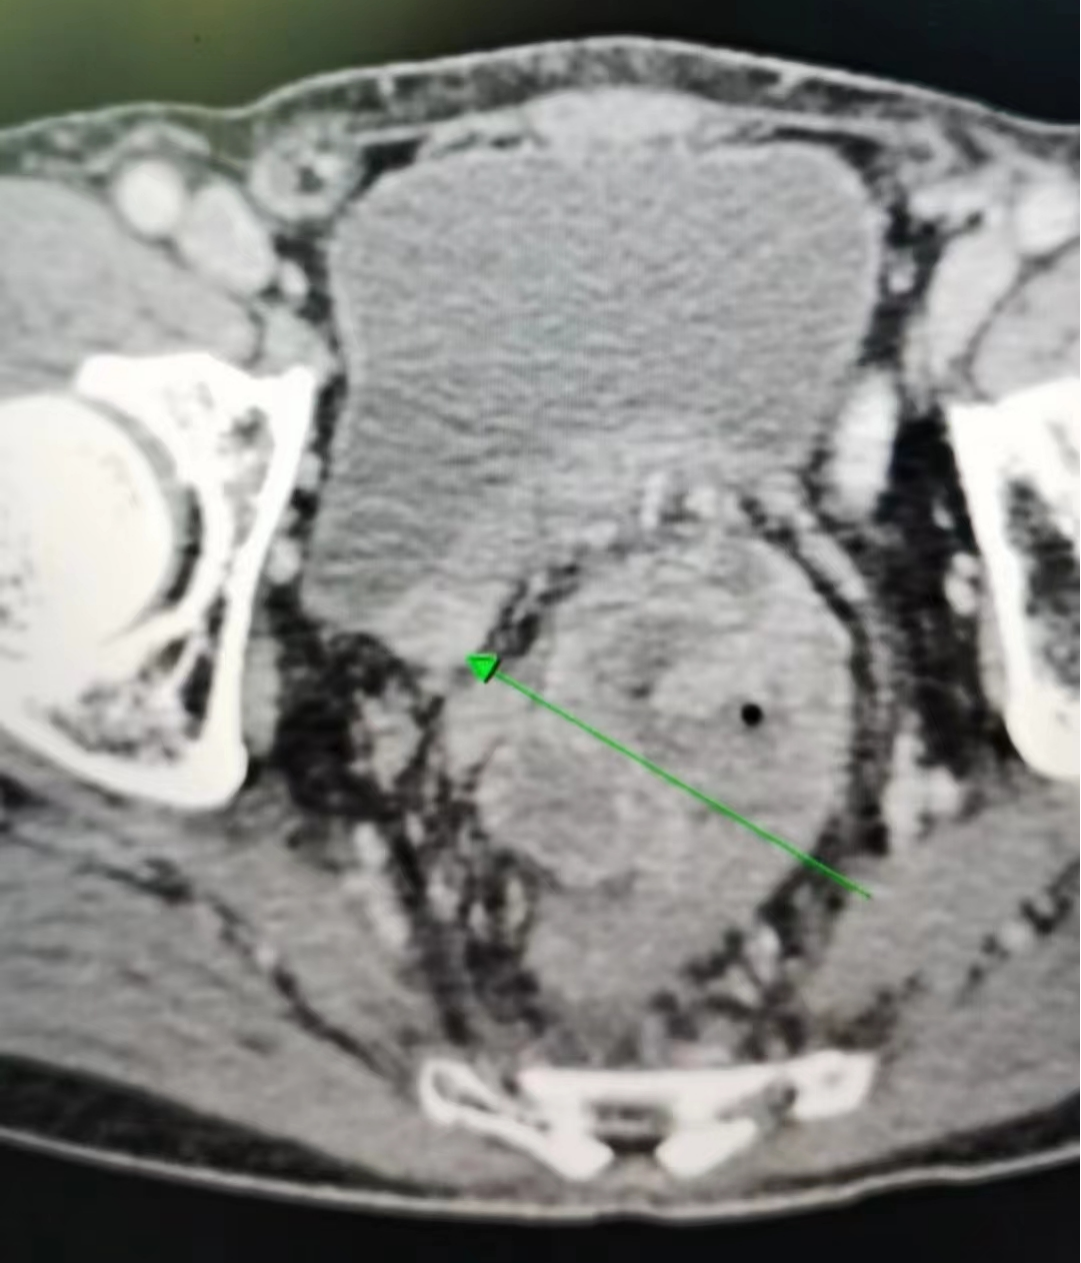

一位80岁高龄患者在一年余前于家中无明显诱因下突发腹部胀痛不适,疼痛呈阵发性,不剧,当时未予以重视。之后反复腹胀腹痛一年多,后期每日解大便数次较前增多,且每次解大便不通畅、不尽感明显。由于老年人对该疾病不敏感,一直误以为肠胃炎,没有及时就医。近期上述症状较前明显加重,遂来温州市中心医院就诊住院,查肠镜发现直肠内一较大的不规则隆起肿块,易出血,已造成肠腔狭窄梗阻,肠镜活检病理提示直肠腺癌。且进一步的腹部CT、MRI检查发现直肠肿瘤已明显侵犯右侧输尿管,导致右肾积水、右输尿管明显扩张。

CT检查

难点之二在于患者的肿瘤侵犯盆壁,骶前、右侧髂血管,这两个部位血管丰富,手术难度大,术中采取先用腹腔镜探查,并进行游离的方式,由于肿瘤较大,从病人安全角度考虑,切换成开放手术。